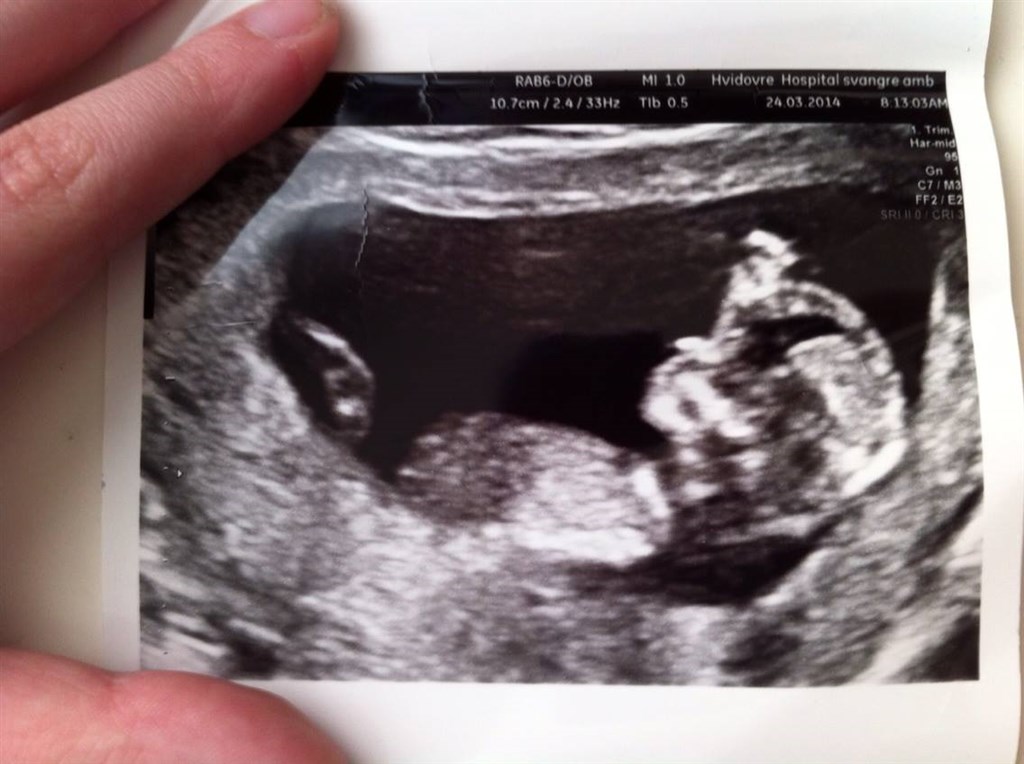

Nakkefoldsskanning veloverstået - hold op, en livlig lille basse der hygger sig ind i maven.

En sød reje på 6.6 cm, meget lille nakkefold, risikotal på 1:7328 og termin er fastsat - d. 30/9-2014

Mormor havde vi snøret, hun troede vi skulle skannes for cyster, så hun græd af lykke inde til skanningen... Det var bare sådan en stor oplevelse.

Nu skal vores dejlige datter være storesøster til efteråret! Hvor fantastisk er det ikke lige!